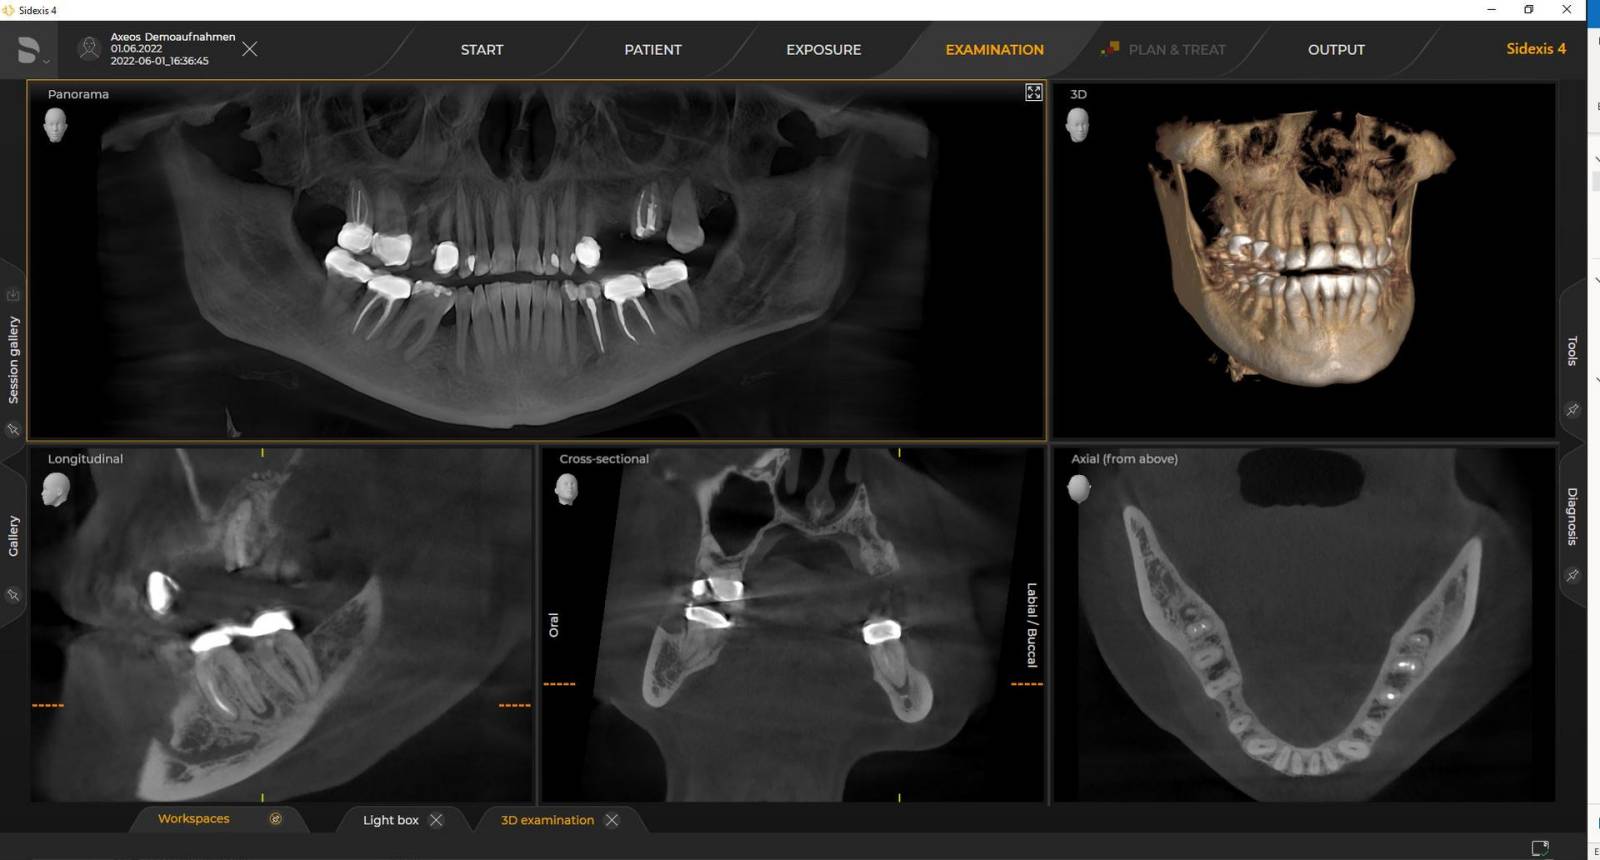

Axeos – the 2D/3D specialist system with a large volume and high image quality for practices with a broad treatment offering. Developed together with dentists and clinicians, Axeos provides the fullest range of functions out of all Dentsply Sirona extraoral X-ray devices. In addition to excellent image quality and tailor-made 3D volume sizes, the dental imaging device is fully optimised for enhanced patient comfort. Axeos not only provides quality in performance and comfort, but also with its award-winning design thanks to the integrated bite block accessory cabinet and ambient light.

Numerous volume sizes ensure flexibility in everyday practice. Examine a precise area or evaluate the complete dentition including the TMJs

With the Intelligent Low Dose mode, you get 3D images in the dose range of a 2D X-ray. In HD mode (up to 1,400) individual images are captured during a single rotation and converted into a 3D volume with up to 80 μm for low-noise images in high resolution

Dentsply Sirona 3D units work exclusively with Sidexis 4. Nevertheless data migration from Sidexis XG to Sidexis 4 is very easy. Sidexis 4 allows for the full digital experience with the latest tools.